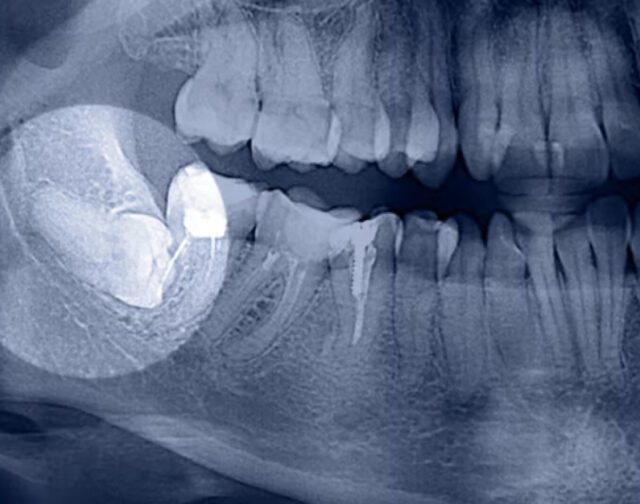

Implants can be placed immediately after tooth extraction. If the socket after extraction is infected, we wait about 2 weeks and do the so-called early delayed implantation. When bone grafting is necessary, implantation is carried out 4 months after the extraction.